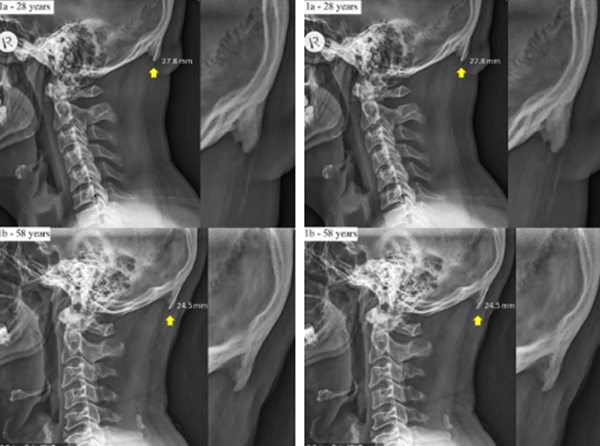

Khối u chẩm ngoài mở rộng có thể mô tả như một chiếc gai, một cục xương thừa lạ lùng mọc nối dài thêm ở khu vực đáy sọ, gần thùy chẩm, tức phía gáy của bạn. Và những người trẻ tuổi đang phát triển chúng nhanh hơn, phổ biến nhất ở những người từ 18-30 tuổi.

Khối u chẩm ngoài mở rộng vẫn xuất hiện dưới hình dạng phần gai xương nối dài thêm